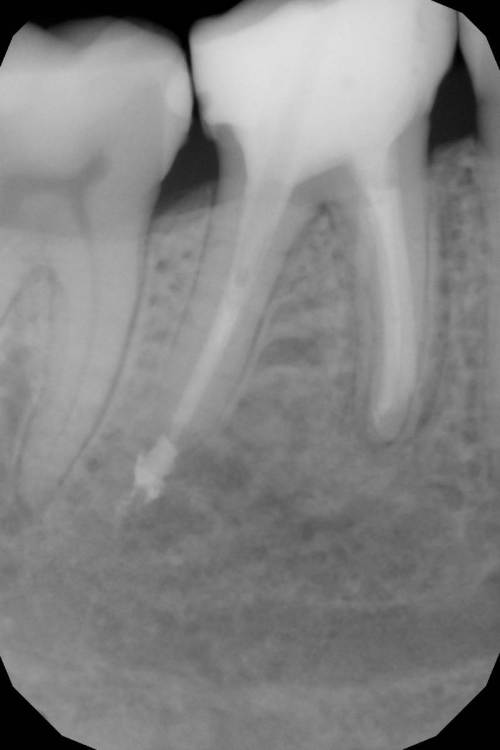

Перфорация. Симметрия каналов. Периодонтит

Как эта перфорация образовалась история умалчивает, оно и не важно, и так видно. Асимметричное расположение корневых каналов всегда наводит на мысли о неправильно раскрытом устье.

Перфорация закрыта триоксиденом, очень классный материал, и главное – наш!))

кальцием пафнуло дистально